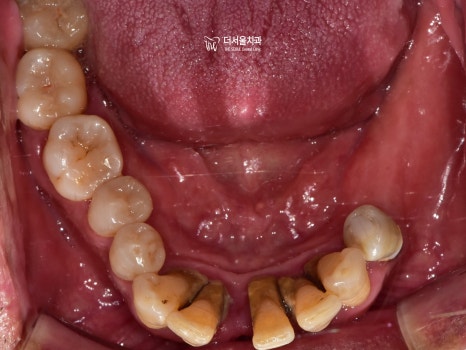

3) 교합면

발치를 하셨기 때문에 텅 비어 있는 곳이 많았습니다.

하악 전치부 쪽이 심각한 것으로 판단이 되네요.

보시다시피 하악 전치부의 문제들이 심각했습니다.

그러나 이쪽에는 또 다른 문제가 있었는데요.

심한 치주 질환으로 공간적으로 뼈가 너무 없었습니다.

즉, 픽스처를 심기에는 어려움이 있다는 뜻이죠.